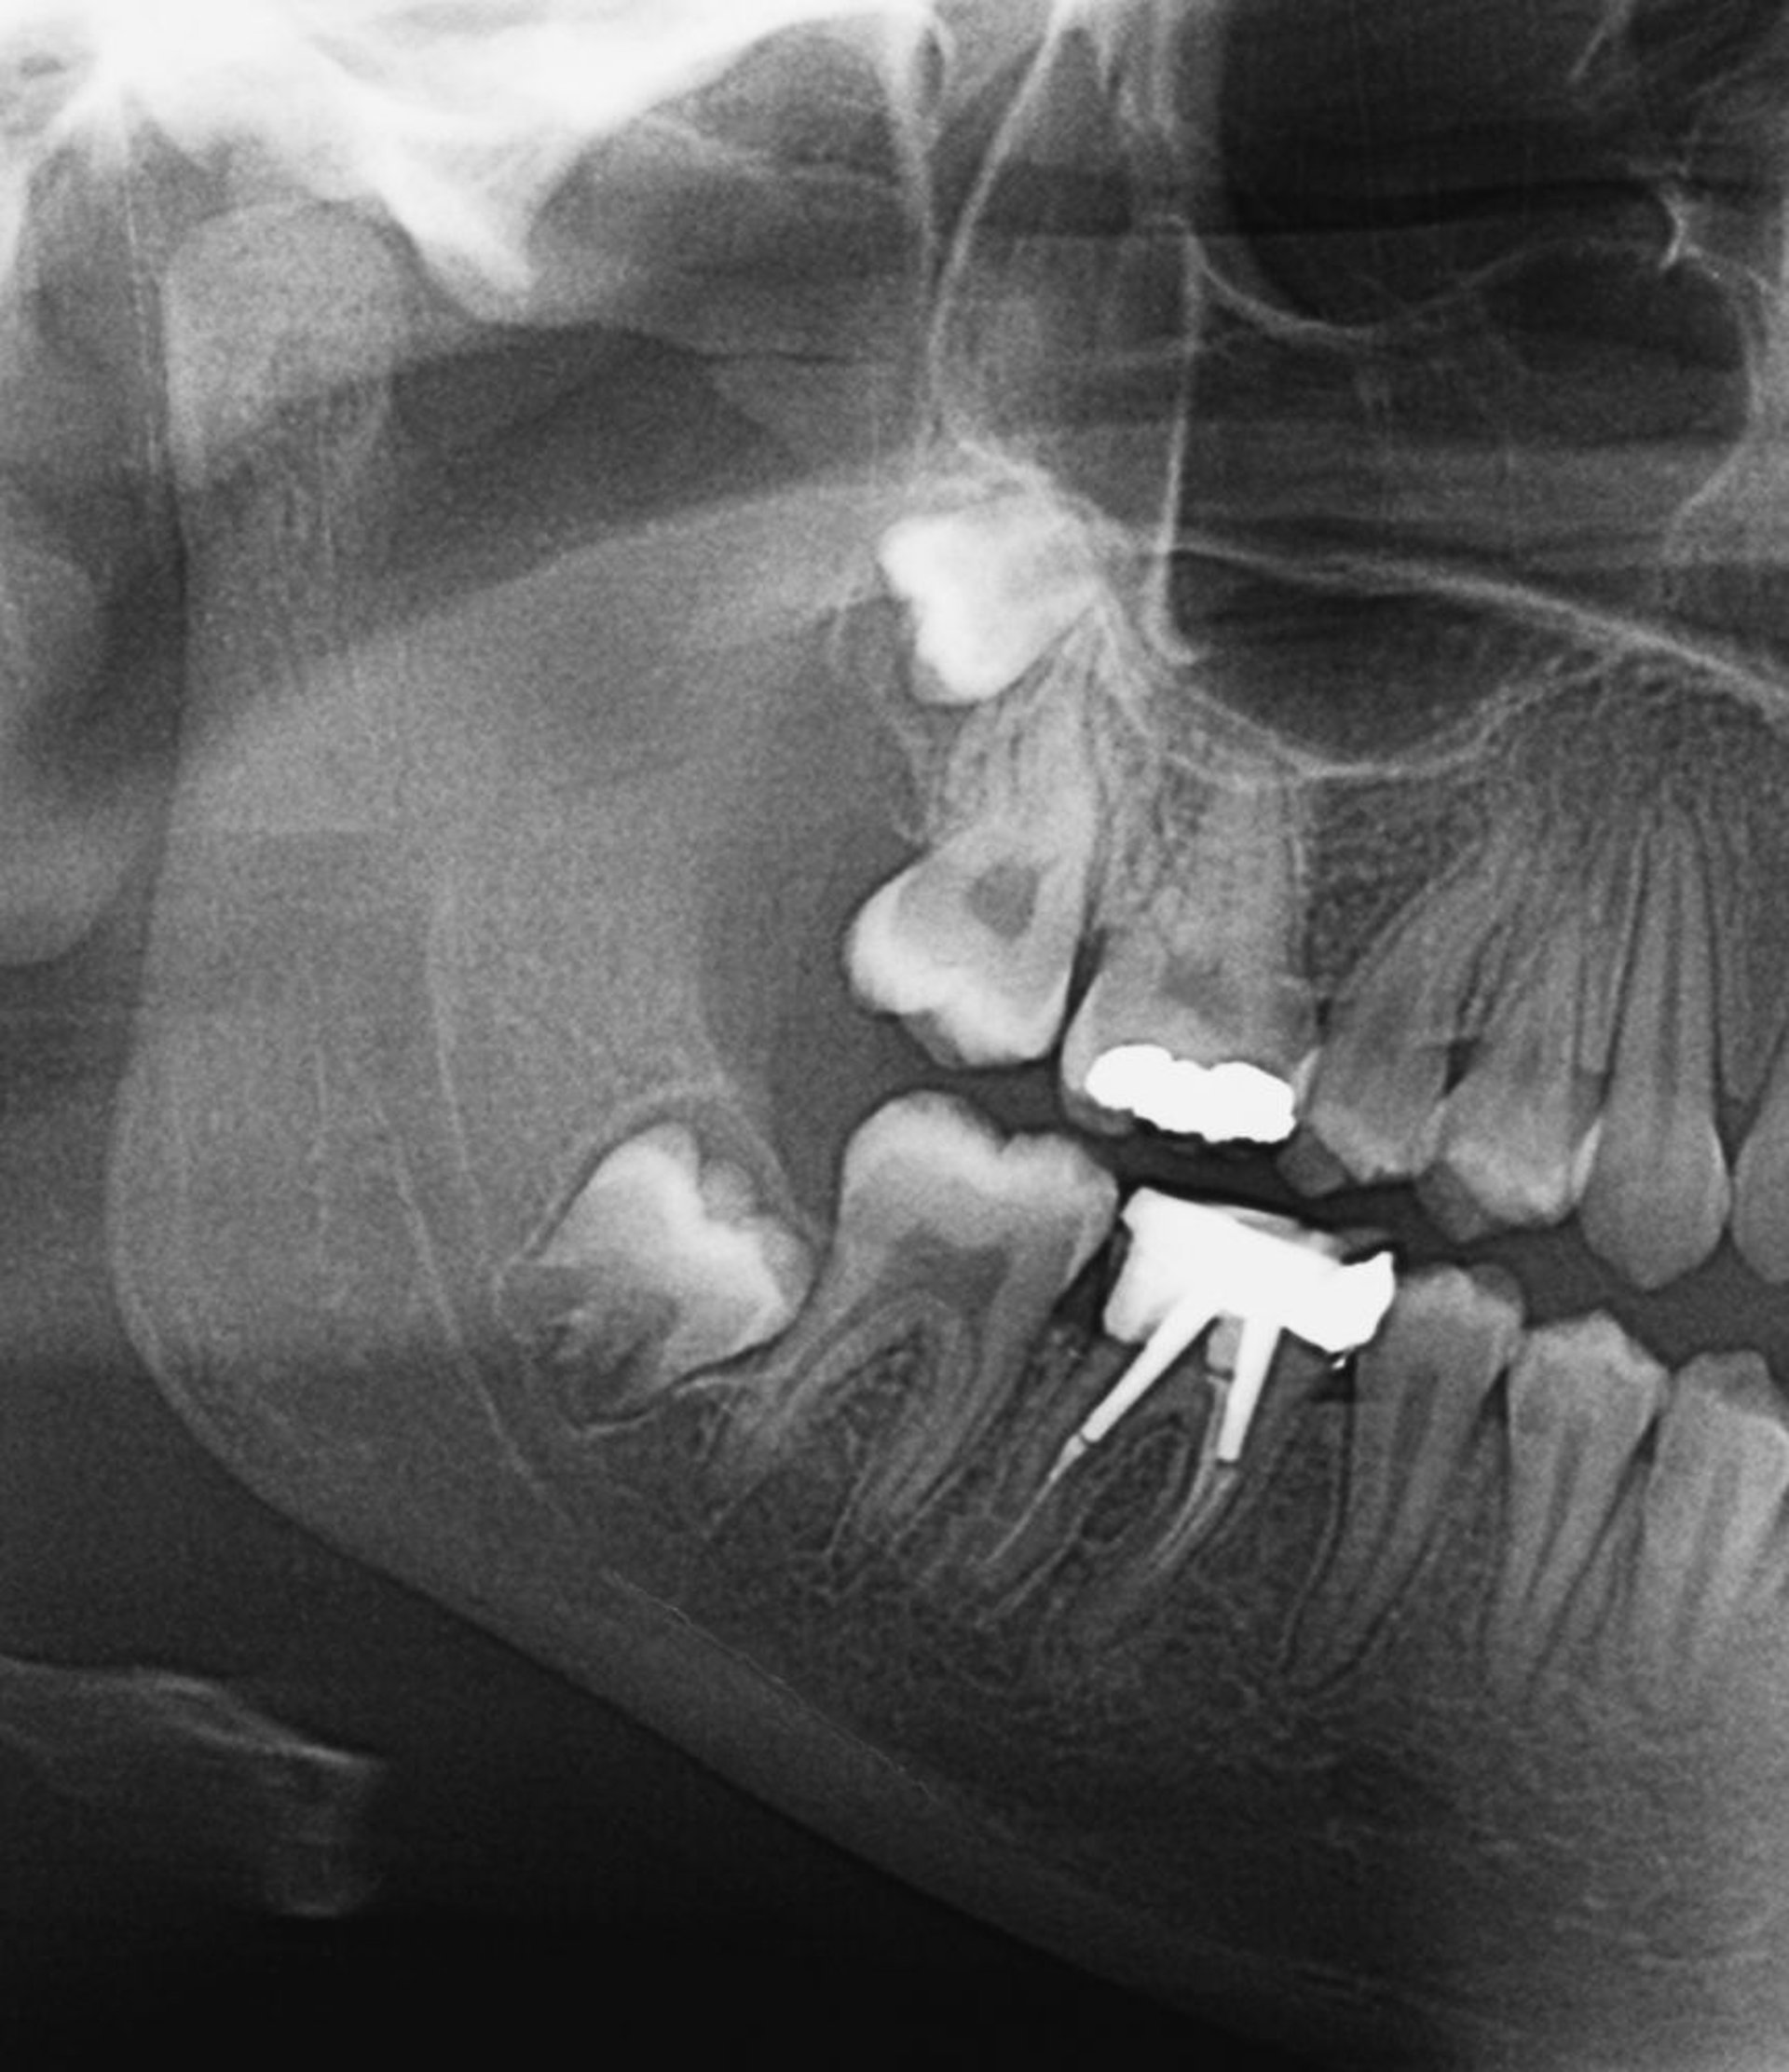

На этом рентгеновском снимке представлены ретинированные зубы мудрости. Перикорониты могут развиваться при прорезывании зубов мудрости или при их частичной ретенции.